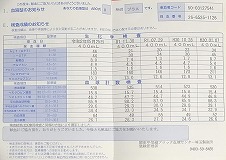

0107 ④2021.11.30=pdf ③2020.05.25 45回目 ②2019.7.29 献血43回目

④

③

③ ②

② ①

①

0106 ③2021.08.23 =PDF

③